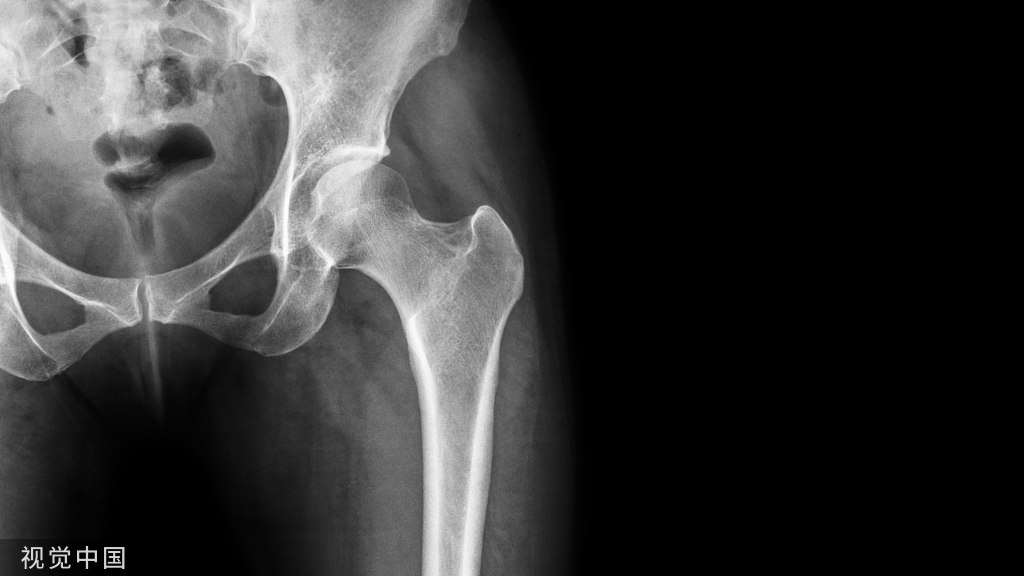

病例简介:患者,男,19岁。因车祸致伤左髋部,伤后4小时来北京积水潭医院急诊,经体检拍片(图62-1),诊断为股骨颈骨折(左,GardenⅣ型)。

图62-1 股骨颈骨折患者术前及术后系列X线片A、B.术前正侧位X线片;C、D.术后当日正侧位X线片;E、F.术后10周正侧位X线片,显示骨折已愈合